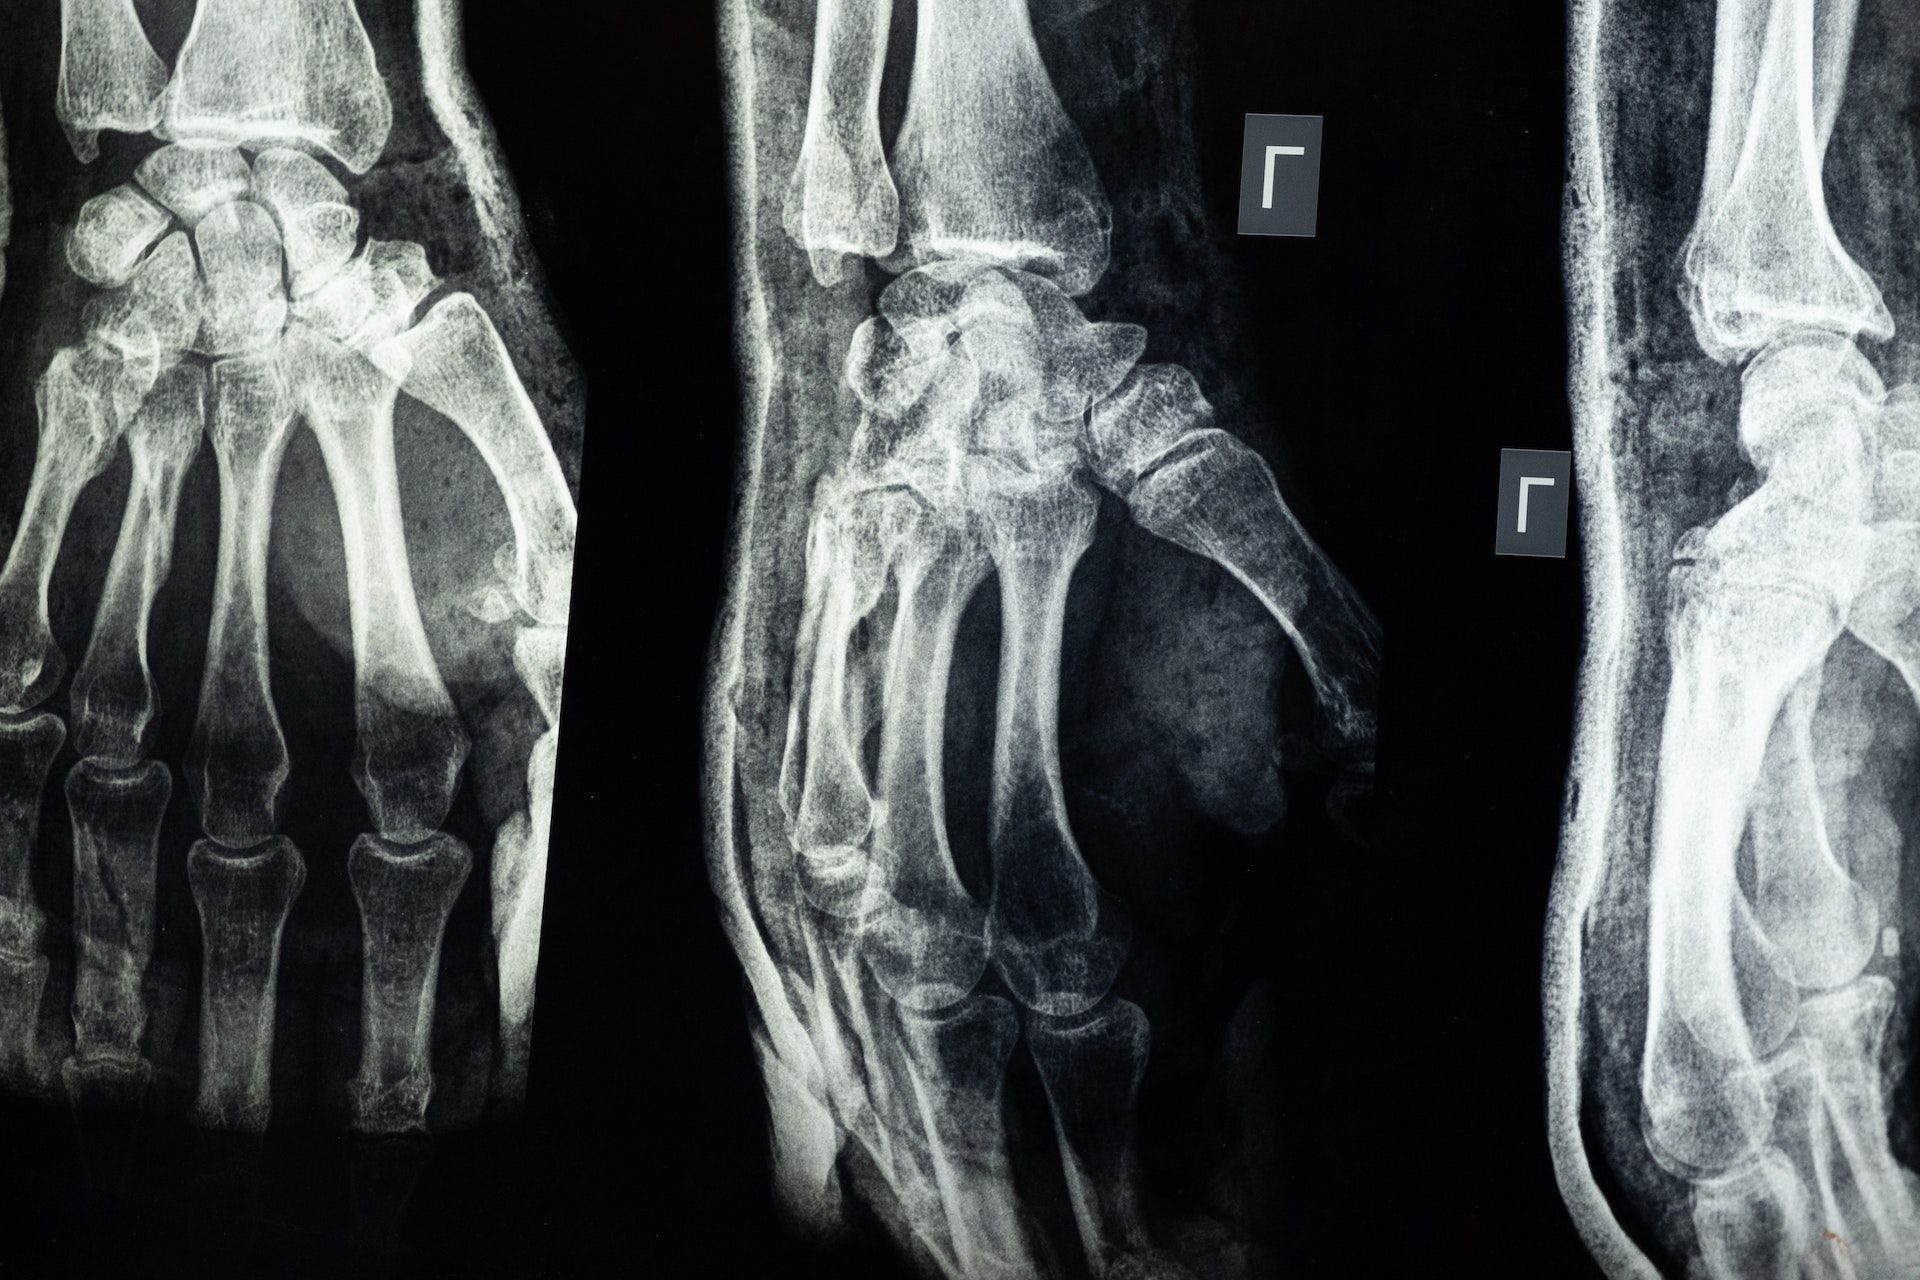

类风湿性关节炎是一种慢性、不断进展的免疫发炎性关节疾病,主要侵犯四肢小关节,但全身的关节皆可受到影响,可能会造成不可回复的关节伤害甚至残疾。是因免疫系统出了问题,自身抗体及发炎物质侵犯关节处,通常表现在对称手脚关节,还有可能侵犯其他的器官,如肝脏、心脏、肺脏、神经系统等,是非常难缠的疾病,需要长期调养和细心照顾。

类风湿性关节炎初期表现为一个或数个关节肿胀和疼痛,具有对称性,会出现滑囊膜发炎,同时伴随晨间关节僵硬,少数人有疲倦、恶心、无力或骨头肌肉酸痛等症状。关节疼痛肿胀是类风湿性关节炎最主要的明显症状,关节僵硬则出现于长期间不活动之后,例如清晨刚睡醒时,且会产生关节积液,严重时会开始压迫神经、侵蚀软骨和硬骨而造成关节变形。除了关节被侵犯外,类风湿性关节炎患者还可能会伴随以下其他症状,例如类风湿结节、巩膜炎、血管炎等,罹患心血管疾病和骨质疏松症的风险也会随之增加。

关节的X光检查存在病变

因旧有的类风湿性关节炎诊断标准需耗时6周,且骨骼需有明显的损害,使得诊断时间太晚,错失治疗的黄金时机,因此欧美风湿医学界于2010年共同发表了新版的诊断标准,利用了不同的评估方式缩短诊断时间,筛选出高风险病人,并及早给予治疗。